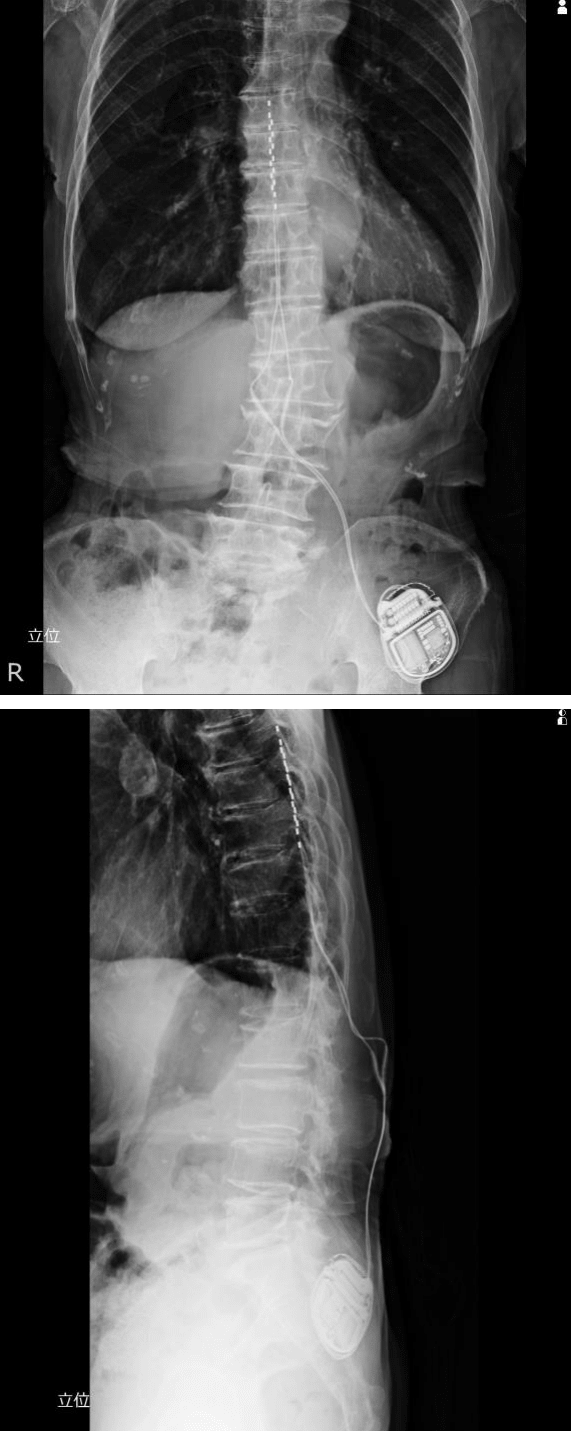

Figure 4 The procedure during surgery. The patient is placed prone while the electrodes are placed under local anesthesia, guided by fluoroscopy (front and side views). Saline is used for subdural insertion using the resistance loss method, and the electrodes are placed on the dorsal column of the spinal cord. Electrical stimulation is applied from an external tablet to confirm paresthesia. Charging is cordless for ease of use.